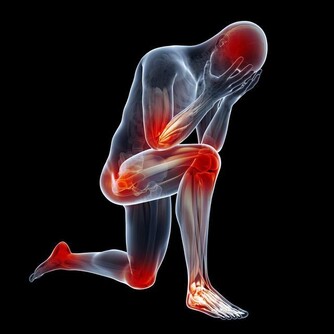

3、疲勞嗜睡

肝不好會導致肝細胞大量壞死,進而引起血清轉氨酶增高,膽鹼脂酶降低,會引起乏力、疲勞、嗜睡等症狀。

- 不明原因乏力、疲倦(沒有過度工作和運動)